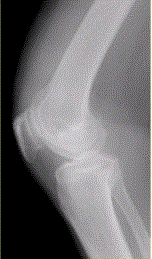

问题 患者女,54岁,右膝关节痛。实验室检查:类风湿因子阳性,除外膝关节类风湿性关节炎。X线检查结果如下图。 MRI结果如下图,诊断应为

选项 A.膝关节退行性骨关节炎 B.膝关节类风湿性关节炎 C.膝关节色素沉着绒毛结节性滑膜炎 D.膝关节滑膜型结核 E.血清阴性脊椎关节炎膝关节侵犯

答案 B